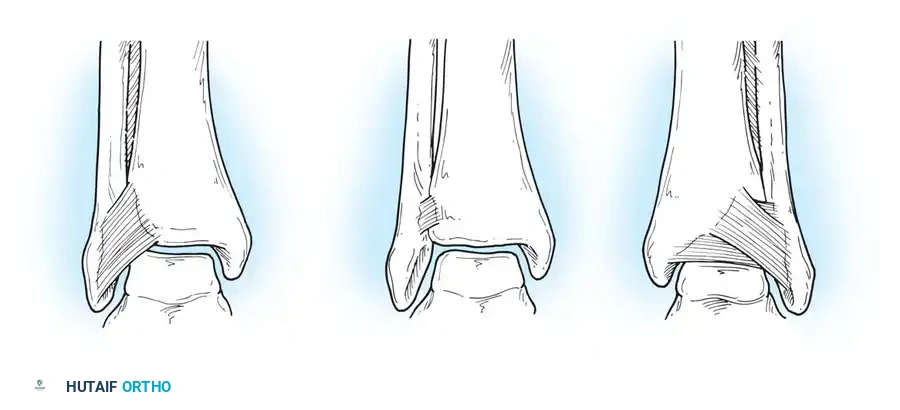

Inversion and Eversion Stress Tests (Talar Tilt)

Complete rupture of the deltoid ligament, including the deep portion, is rare in isolation. When the deltoid is completely ruptured in conjunction with a syndesmotic tear or lateral malleolus fracture, the talus shifts laterally with eversion stress.

If the lateral ligaments are completely disrupted, the talus tilts abnormally within the mortise under inversion stress. This stress is best applied with the ankle in slight plantarflexion to isolate the ATFL.

- Bonnin's Criteria: A talar tilt of 15 degrees indicates isolated ATFL rupture; 15 to 30 degrees indicates combined ATFL and CFL rupture; >30 degrees indicates rupture of all three lateral ligaments.

- Black's Criteria: Found no absolute clear-cut endpoint but noted that a talar tilt of less than 10 degrees is generally consistent with an isolated ATFL injury.

Hollis et al. noted that if an anteroposterior drawer test shows less laxity in dorsiflexion than in neutral, an isolated ATFL tear is likely. Conversely, laxity present in both 15 degrees of dorsiflexion and neutral indicates combined ATFL and CFL disruption.